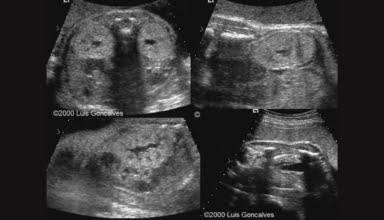

[Video] Dị tật hệ niệu, Bs Hà Tố Nguyên

Dị tật hệ niệu là bài giảng trong Khóa học Siêu âm Sản phụ khoa (BV Từ Dũ) do Bs Hà Tố Nguyên giảng dạy.